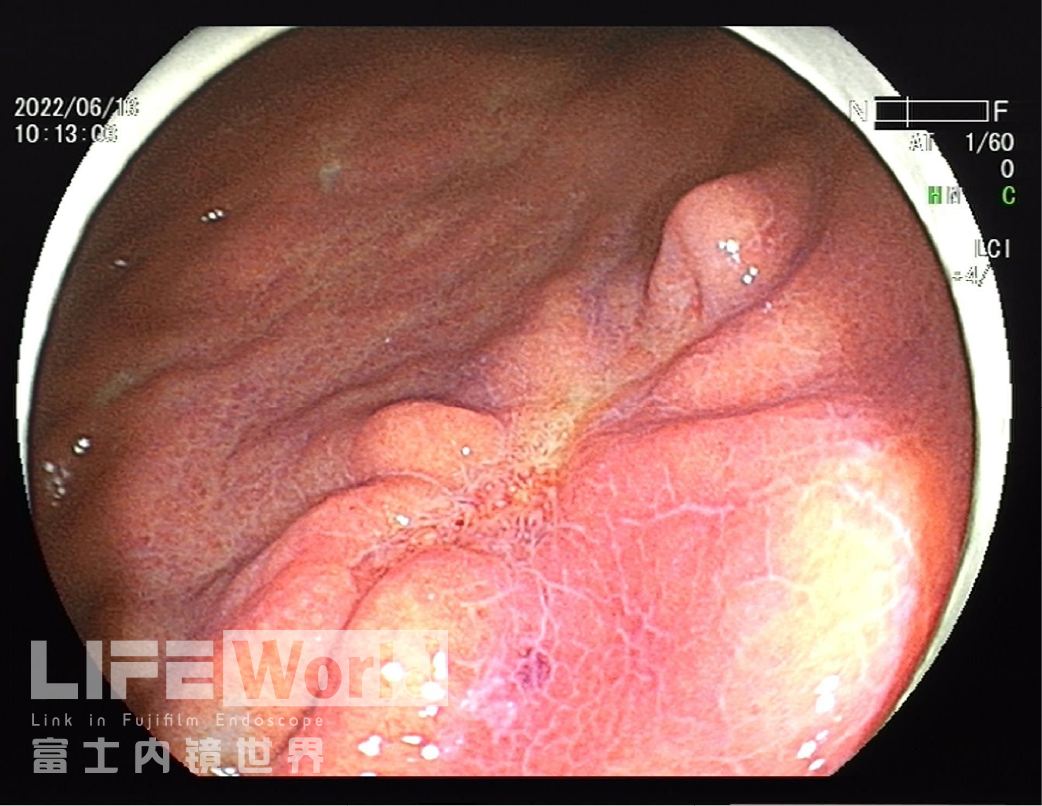

白光观察:胃体下段大弯侧可见一处中央凹陷的病变,色红,范围约1.2×0.6cm,周围黏膜集中、中断。

LCI模式:病变为橙黄色,周围黏膜呈紫红色。

该病变位于胃体下部大弯侧,病变大体分型为IIc型,病灶较小,有时候受皱襞影响不易发现,注气不充分时易漏诊,白光下给出了远景、中景及近景照片,并通过气体量的变化展现了不同注气状态下的病变形态,病变有皱襞集中、中断,未见皱襞融合现象,部分区域色泽发红,另外对病变肛侧端微小的粘膜变化也没放过,观察的很仔细,留图很规范。

2、LCI是富士内镜鲜明和实用的技术,在LCI下看凹陷区域实际是分为3个部分,口侧及肛侧偏后壁两处在LCI下更加的发红,呈不规则的红黄混杂,而中央的区域呈发白色调。结合凹陷周边黏膜的紫色肠化的病变发生背景,符合紫包红/黄的早癌表现,更加有利于在非放大下识别及初步诊断病变性质。中央发白区域提示修复可能性大;